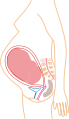

Prenatal development and sonograph images

Prenatal development is divided into two primary biological stages. The first is the embryonic stage, which lasts for about two months. At this point, the fetal stage begins. At the beginning of the foetal stage, the risk of miscarriage decreases sharply, all major structures including hands, feet, head, brain, and other organs are present, and they continue to grow and develop. When the fetal stage commences, a fetus is typically about 30 mm (1.2 inches) in length, and the heart can be seen beating via sonograph; the fetus bends the head, and also makes general movements and startles that involve the whole body. Brain stem activity has been detected as early as 54 days after conception, and the first measurable signs of EEG activity occur in the 12th week. Some fingerprint formation occurs from the beginning of the fetal stage.

One way to observe prenatal development is via ultrasound images. Modern 3D ultrasound images provide greater detail for prenatal diagnosis than the older 2D ultrasound technology. Whilst 3D is popular with parents desiring a prenatal photograph as a keepsake, both 2D and 3D are discouraged by the FDA for non-medical use, but there are no definitive studies linking ultrasound to any adverse medical effects. The following 3D ultrasound images were taken at different stages of pregnancy: